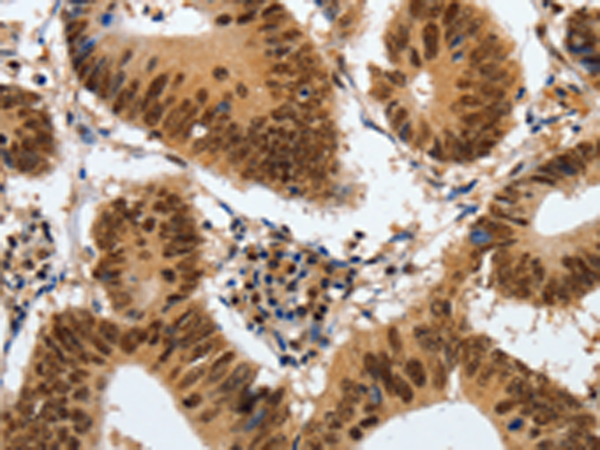

分类: 科研抗体货号: P00534别名: MI; WS2; CMM8; WS2A; COMMAD; bHLHe32应用: WB,IHC反应种属: Human, Mouse, Rat